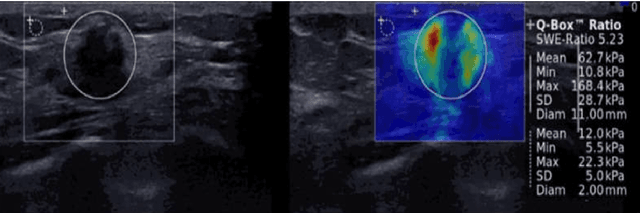

In the last decade, researchers working in the domain of computer vision and Artificial Intelligence (AI) have beefed up their efforts to come up with the automated framework that not only detects but also identifies stage of breast cancer. The reason for this surge in research activities in this direction are mainly due to advent of robust AI algorithms (deep learning), availability of hardware that can train those robust and complex AI algorithms and accessibility of large enough dataset required for training AI algorithms. Different imaging modalities that have been exploited by researchers to automate the task of breast cancer detection are mammograms, ultrasound, magnetic resonance imaging, histopathological images or any combination of them. This article analyzes these imaging modalities and presents their strengths, limitations and enlists resources from where their datasets can be accessed for research purpose. This article then summarizes AI and computer vision based state-of-the-art methods proposed in the last decade, to detect breast cancer using various imaging modalities. Generally, in this article we have focused on to review frameworks that have reported results using mammograms as it is most widely used breast imaging modality that serves as first test that medical practitioners usually prescribe for the detection of breast cancer. Second reason of focusing on mammogram imaging modalities is the availability of its labeled datasets. Datasets availability is one of the most important aspect for the development of AI based frameworks as such algorithms are data hungry and generally quality of dataset affects performance of AI based algorithms. In a nutshell, this research article will act as a primary resource for the research community working in the field of automated breast imaging analysis.